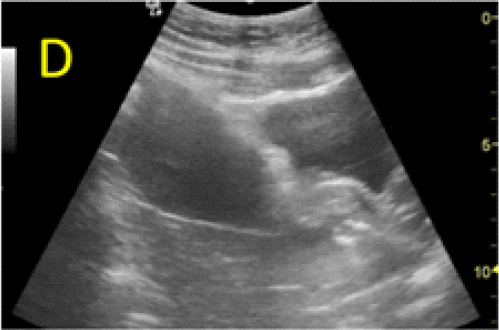

Figure 4. Local administration of MTX procedure. The aspect before injection (A), insertion of the needle in the uterine wall (B) and the trophoblast (C). Injection of the MTX in the trophoblastic area (D) and progression of the needle in the embryonic area of the gestational sac (E) with the administration of the rest of the dose (F) reported value of 103.016mUI/ml. Ultrasound

We considered that the initial protocol failed to fulfill its purposes, and because of an imminent severe complication, we decided further active management. Using transabdominal ultrasound guidance, with a thin 22-Gauge needle, 25 mg of MTX ware injected transvaginally in the gestational sac, in the embryonic area and another 25mg of were injected in the trophoblastic tissue (Figure 4). To reduce the patient’s discomfort and anxiety, local methotrexate injection under transvaginal ultrasound guidance was performed under general anesthesia with the patient in the lithotomy position. 24 hours later the scan confirmed that the fetal cardiac activity ceased.